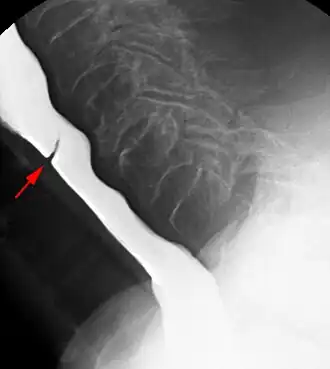

Esophageal web stenosis in barium swallow examination lateral view. -

Esophageal web stenosis in barium swallow examination frontal view.

The diagnostic test of choice is a barium swallow.